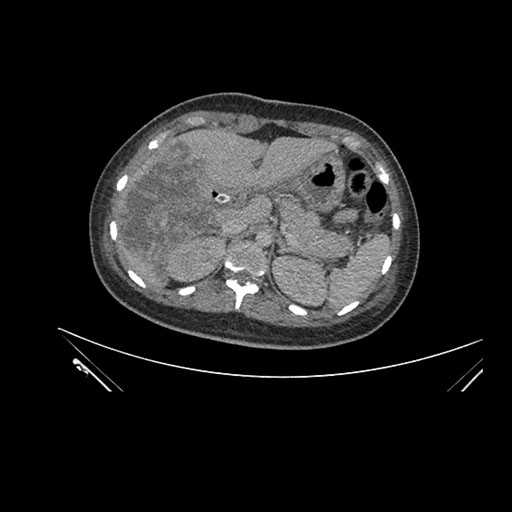

Imaging Analysis

Look through the patient's CT scan to identify any areas of concern for the necessary procedure.

Axial Venous